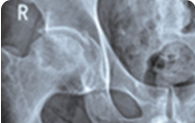

治疗前:股骨头塌陷明显,骨质受损严重,关节间隙变窄

治疗中:股骨头受损骨质开始自我修复,关节间隙逐渐正常

治疗后:股骨头骨质修复完整,关节间隙正常